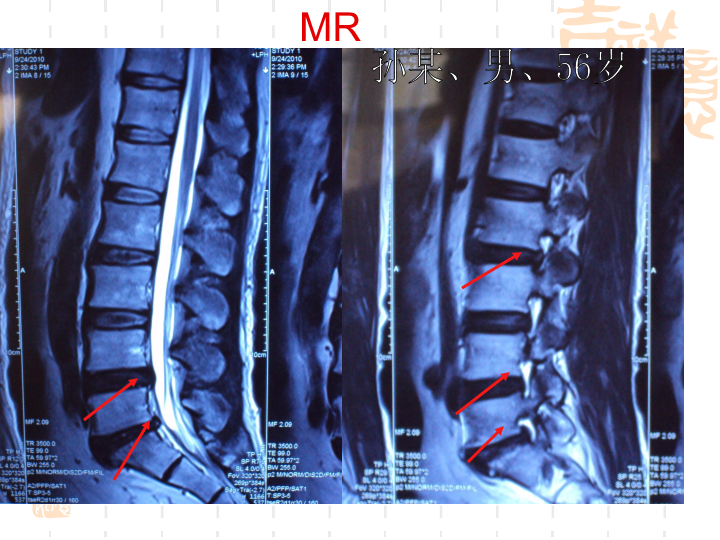

椎间盘突出